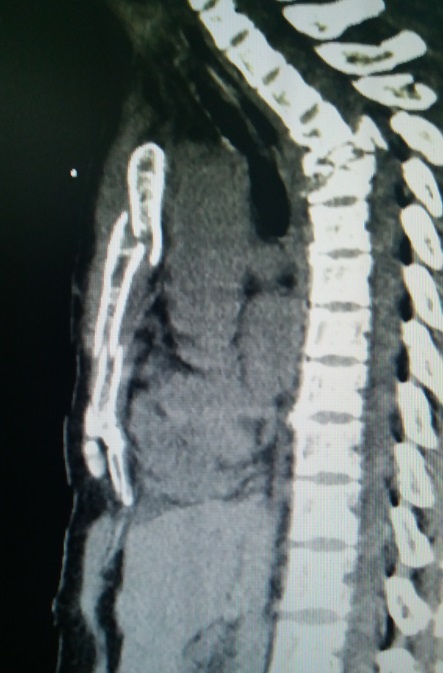

术前行X线检查,提示胸椎骨折固定术征象,左侧第2、3后肋骨折。行CT检查,提示胸骨两处骨折,其中上位骨折位于胸骨角,骨折上半胸骨嵌入下半胸骨后方。三维重建提示胸骨骨折,前胸壁凹陷畸形。

图2,CT检查:胸骨两处骨折,前胸壁上方凹陷。